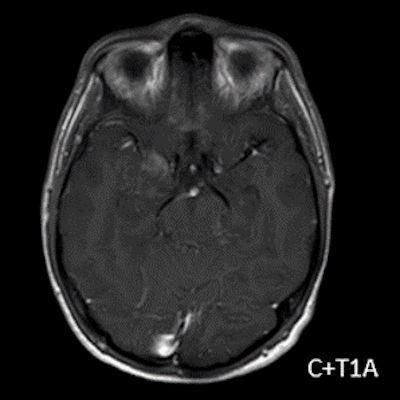

- A) Sağ temporal lob anteromedialinde silik sınırlı BT’de hipodens (ok), MRG’de T2AG ve FLAIR hiperintens (oklar), T1AG izo-hipointens (ok) sinyal özelliğinde ekspansil kitlesel lezyon izlenmektedir.

- B) Lezyon difüzyon görüntüde izo-hiperintens, ADC haritalamada hafif hiperintens izlenmiş olup (oklar) diffüzyon kısıtlılığı göstermemektedir. Lezyonun anterior kesiminde kontrastlı serilerde yamalı kontrast tutulumları (oklar) mevcuttur. MR spektroskopide lezyon düzeyinden elde olunan multivoksel görüntülerde kolin pikinde artış ve NAA da azalma (oklar) dikkati çekmektedir. Kolin/kreatinin oranı 1.76 olarak ölçülmüştür.

- MRG: T1A serilerde solid komponent izo-hipointens, T2A serilerde genellikle hiperintens sinyalde görülür. Peritümöral T2/FLAIR hiperintens kitle ödemi oldukça nadirdir. T1 C+ görüntülerde solid komponentte değişken oranda kontrastlanma ,T2*(SWI) serilerde eğer kalsifikasyon eşlik etmekteyse buna bağlı blooming artefaktları görülebilir.